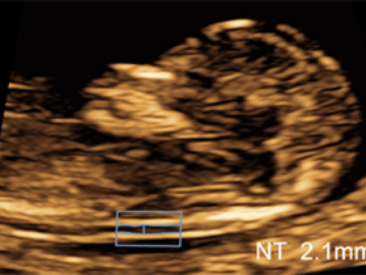

Obrazy kliniczne